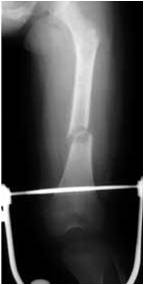

Fractura de la diáfisis de los huesos largos

Niño de 5 años. El novio de la madre confesó haberlo lanzado contra un televisor